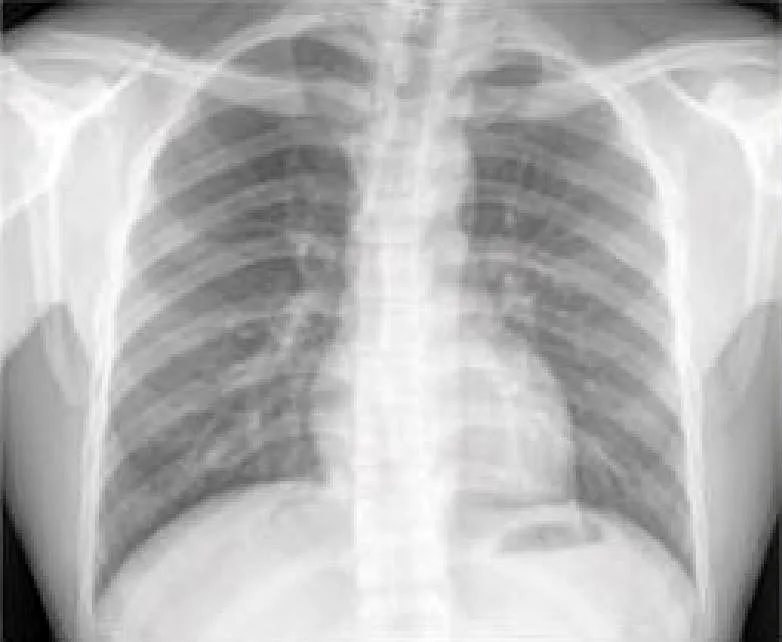

محققان یک مدل یادگیری عمیق طراحی کردهاند که با استفاده از تصاویر تهیهشده از طریق رادیوگرافی قفسه سینه، خطر مرگ ناشی از سکته قلبی یا مغزی ناشی از بیماری قلبیعروقی آترواسکلروتیک را تا ۱۰ سال آینده پیشبینی کند.

یادگیری عمیق نوعی هوش مصنوعی پیشرفته است که میتوان آن را آموزش داد تا تصاویر حاصل از رادیوگرافی را بهمنظورِ یافتن الگوهای مرتبط با بیماری جستوجو کند. به گفته جِیکوب وِیس (Jakob Weiss)، پزشک و یکی از اعضای تیم پژوهشی، این مدل یادگیری عمیق، راهحلی بالقوه برای شناسایی افراد مستعد بیماریهای قلبیعروقی با استفاده از تصاویر حاصل از رادیوگرافی قفسه سینه ارایه میکند. با این روش مشخص میشود چه کسانی در ۱۰ سال آینده به دلیل بیماریهای قلبیعروقی در خطر خواهند بود و برای پیشگیری از آن باید استاتین دریافت کنند.

ویس گفت: ما نشان دادیم که رادیوگرافی قفسه سینه بیش از یک عکسبرداری است. با چنین روشی، یک اندازه کمّی بهدست میآوریم که به ما این امکان را میدهد که برای کمک به پزشک و بیمار، هم اطلاعات تشخیصی و هم پیشآگاهی ارایه کنیم.